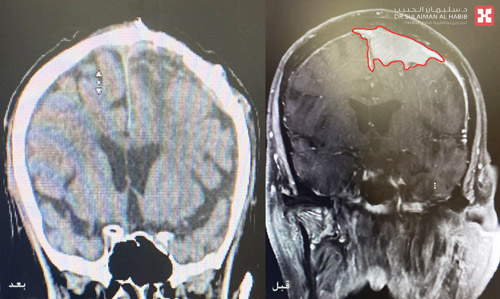

وقد كشفت الفحوصات الدقيقة التي أجريت له عن وجود ورم كبير بحجم (6×5×6) سم متمركز في منتصف الدماغ بالقرب من مراكز منطقة الحركة للأطراف العلوية والسفلية ومتداخل مع الشريان الأعظم، ونتج عنه إزاحة وضغط شديد على الدماغ ووجود انسداد في عدد من الشرايين المحيطة به.

وأضاف د. هاني أن حالة المريض تحسنت في اليوم الثالث وتم نقله لجناح التنويم، مع إخضاعه لفحوصات بالتصوير المقطعي حيث أثبتت استئصال الورم بشكل كامل ونجاح العملية وانتهاء نوبات التشنج والحركات اللاإرادية، وخرج من المستشفى في اليوم الرابع وهو بصحة جيدة.